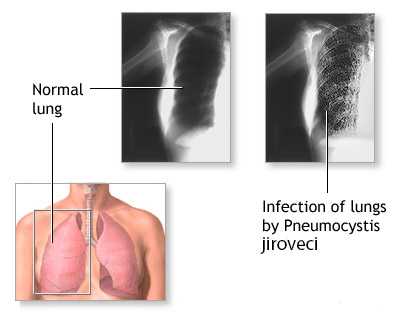

- Рентгенография органов грудной клетки - усиление легочного и сосудистого рисунка, очаговые тени, участки повышенной прозрачности, билатеральные инфильтраты, синдром «вуали» или «снежных хлопьев», расширение легочных корней,

На рентгенограммах и КТ легких в типичных случаях определяется облаковидное понижение прозрачности легочных полей, получившее название «хлопьев снега» или «ватного легкого». Иногда рентгенологические изменения отсутствуют или имеют атипичную картину. С помощью ФВД обнаруживаются признаки дыхательной недостаточности по рестриктивному типу; исследование газового состава крови свидетельствует о гипоксемии.

- Рентгенологические. В начальной стадии пневмоцистной пневмонии на рентгенограммах легких выявляются инфильтраты, похожие на очертания крыльев бабочки. В разгаре инфекции заметны двусторонние симметричные очаги уплотнения, чередующиеся с участками вздутия («ватное» легкое). На КТ грудной клетки обнаруживаются участки инфильтрации по типу «матового стекла».

Рентгенологическая картина при пневмоцистной пневмонии также развивается постепенно:

I стадия - обнаруживаются мелкоочаговые тени в обоих легких, напоминающие крылья бабочки;

II стадия - в легких появляются обильные очаговые тени, местами сливающиеся в крупные участки уплотнения, перемежающиеся участками вздутия. Структура легкого становится «ватной», т.е. по рисунку напоминает тонкий слой ваты с более или менее плотными участками;

III стадия - лобулярные вздутия, расположенные субплеврально, что может привести к их разрыву с образованием серповидного пневмоторакса.